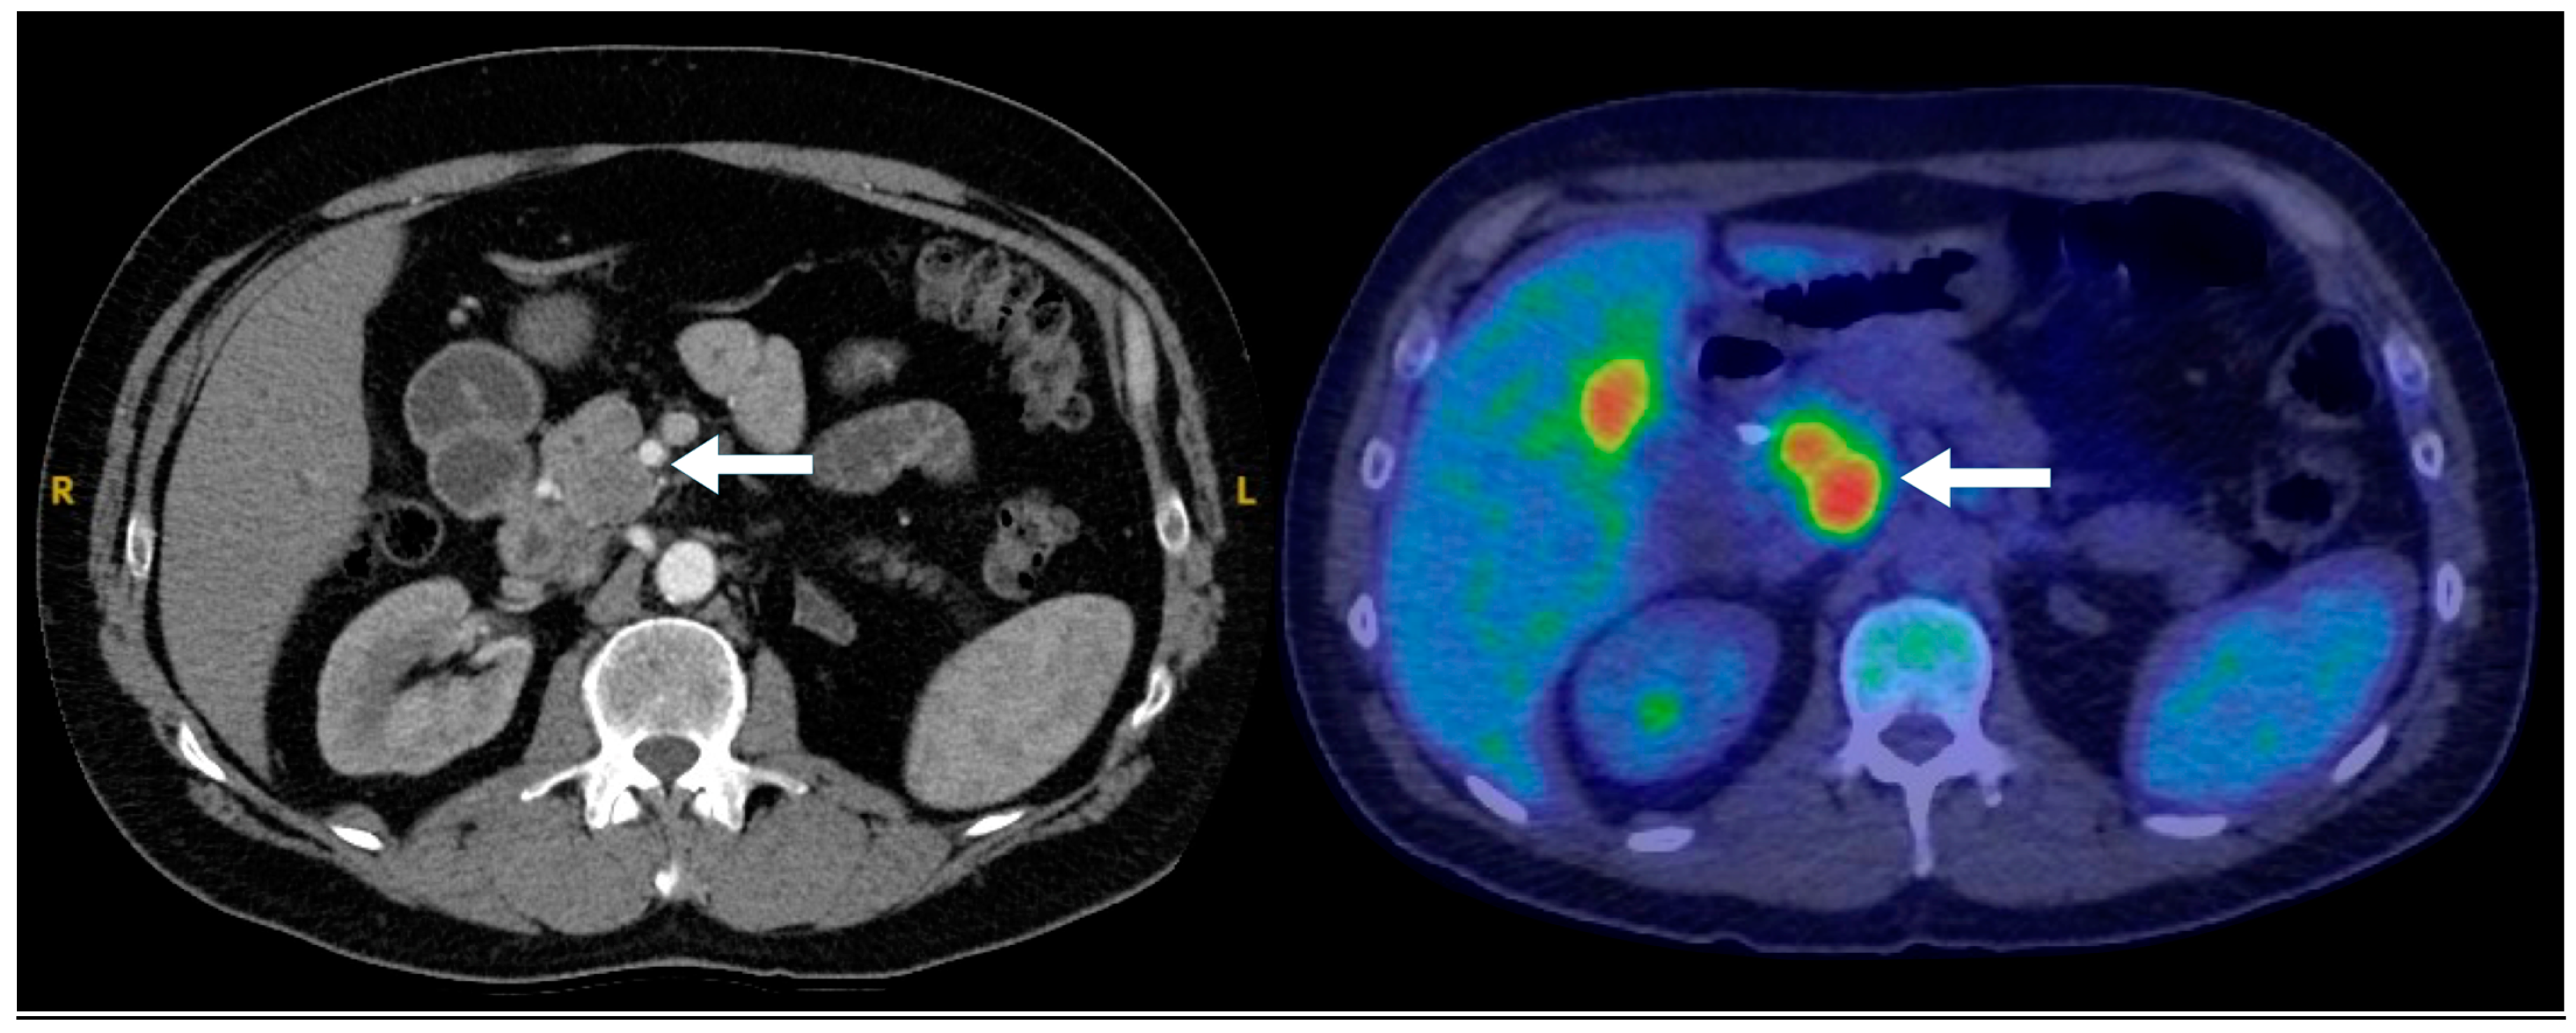

Figure 6. A 47-year-old male presenting with biliary obstruction. CT (left): Arterial phase imaging shows a 2.5 cm hypodense mass in the pancreatic head (arrow). PET-CT (right): Performed after ERCP and biliary stent placement, demonstrating an intensely FDG-avid pancreatic head mass (arrow), consistent with a poorly differentiated primary neuroendocrine tumor. Metastatic disease involving porta hepatis and peripancreatic lymph nodes, as well as liver metastases, is also evident on the PET.

Figure 7. A 47-year-old male presenting with biliary obstruction. H&E stain (left): Biopsy of the pancreatic mass demonstrating a poorly differentiated pancreatic neuroendocrine carcinoma (PNEC) with high cellularity, hyperchromatic nuclei, high nuclear-to-cytoplasmic ratio, and apoptosis. Ki-67 immunohistochemistry (right): A high Ki-67 index, consistent with a high-grade neuroendocrine carcinoma (×200 magnification).